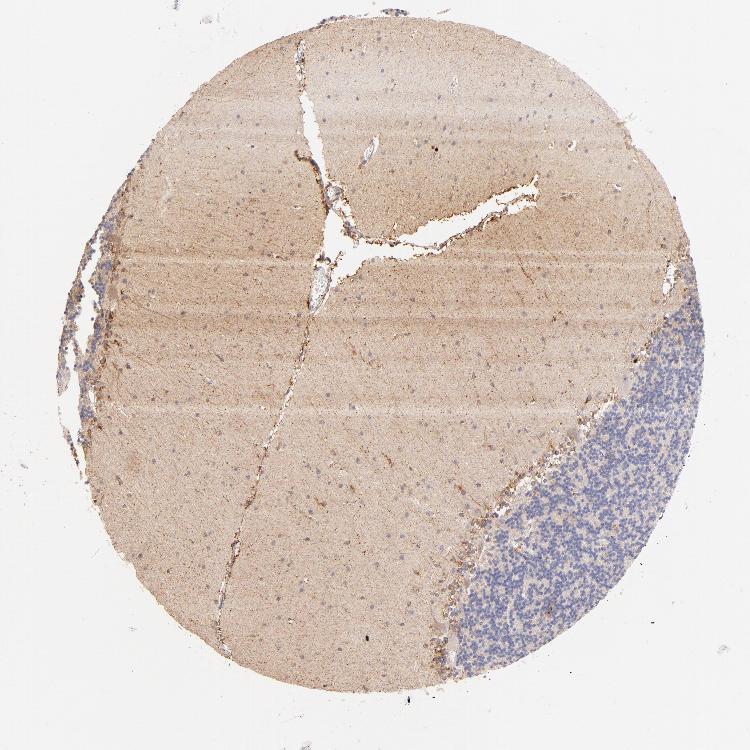

CEREBELLUM - Antibody stainingi

Antibody staining in the annotated cell types in the current human tissue is reported as not detected, low, medium, or high, based on conventional immunohistochemistry profiling in selected tissues. This score is based on the combination of the staining intensity and fraction of stained cells.

Each image is clickable and will lead to virtual microscopy that enables deeper exploration of all samples and also displays staining intensity scores, fraction scores and subcellular localization as well as patient and tissue information for each sample.

Antibody HPA002989Antibody HPA003020Antibody CAB002306

Bergmann glia - cytoplasm/membrane -High-

Cells in molecular layer Not detected-High

Granular cells - cytoplasm/membrane -High-

Molecular layer cells - cytoplasm/membrane -High-

Processes in molecular layer -High-